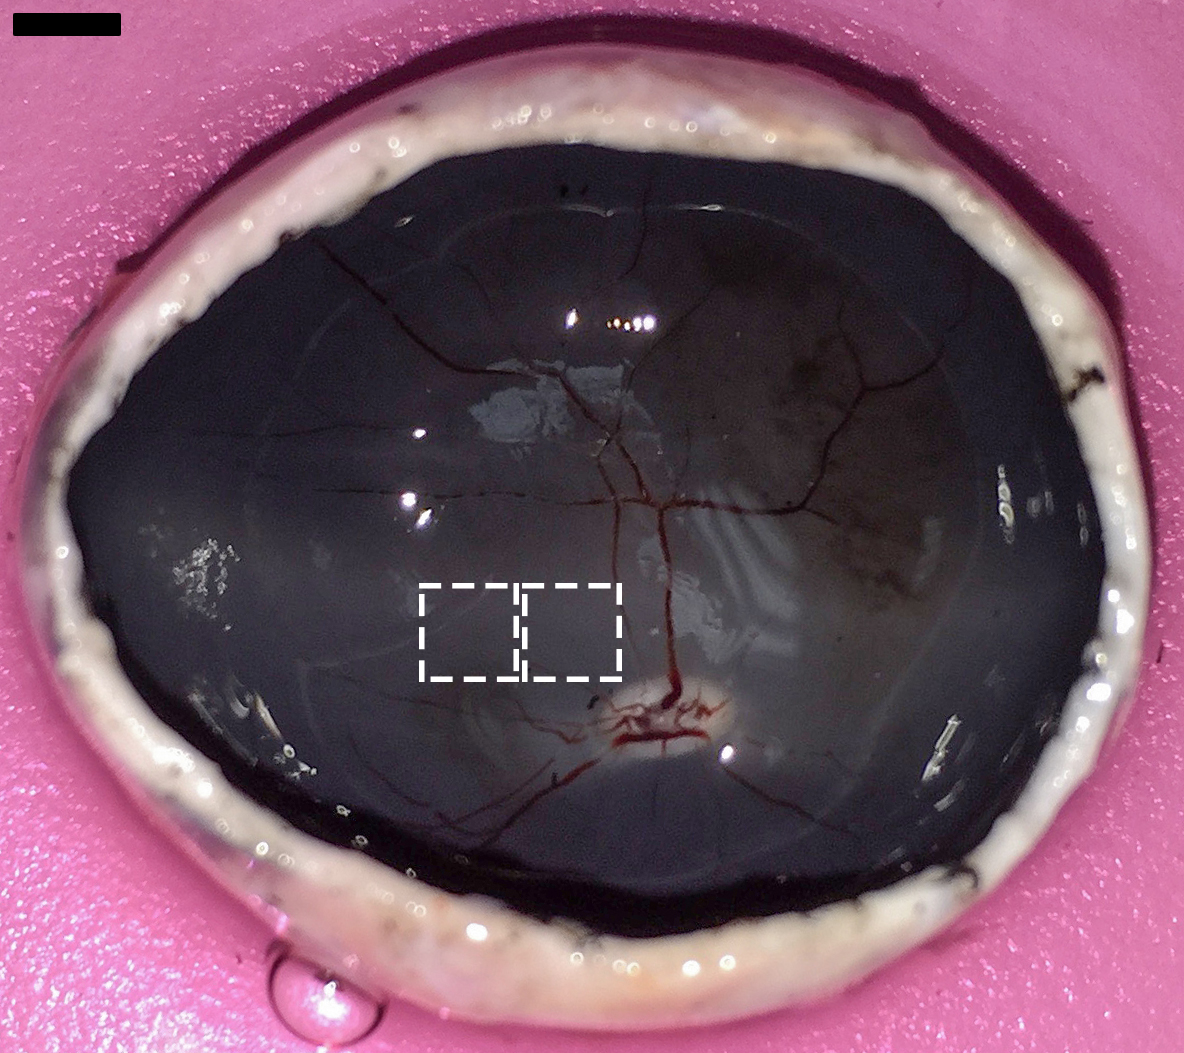

Figure 1 of Di Lauro, Mol Vis 2016; 22:243-253.

Figure 1. Neuroretina explant tissue sampling in porcine globe. Two neuroretina explants (5×5 mm) were obtained from each eye at the porcine cone-enriched visual streak superotemporal to the optic disc. Scale bar=5 mm.